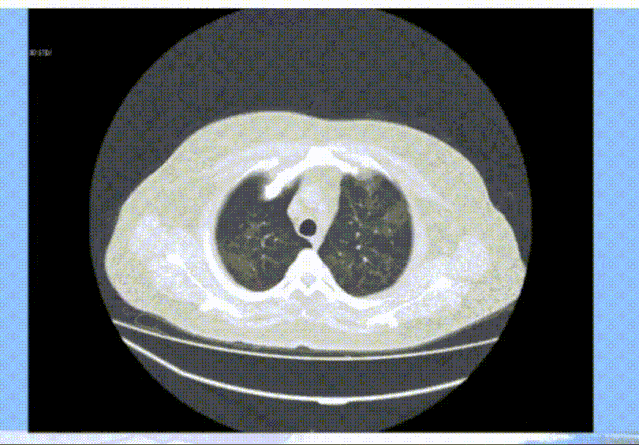

一键自动提取肺气管成像